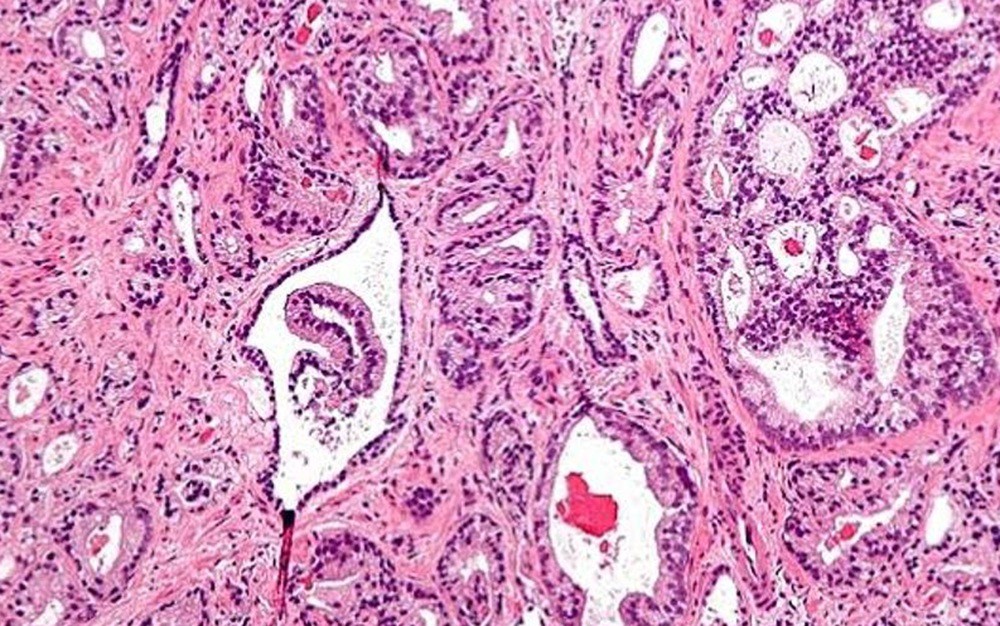

Un reciente estudio liderado por investigadores del Instituto de Salud Carlos III (ISCIII) ha revelado un incremento significativo en el riesgo de desarrollar cáncer de próstata en hombres expuestos a arsénico, especialmente en sus formas más avanzadas y agresivas. Este hallazgo se basa en el análisis de este semi-metal acumulado en las uñas de los pies y forma parte del proyecto MCC-Spain, uno de los estudios epidemiológicos más grandes sobre cáncer realizados en España.

Las conclusiones del estudio han sido publicadas en la revista Environmental Research. El arsénico, un metaloide tóxico que se encuentra de forma natural en el medio ambiente, puede estar presente en el agua potable, ciertos alimentos y algunas actividades industriales. La exposición a este elemento puede tener graves repercusiones para la salud, aumentando el riesgo de varios tipos de cáncer.